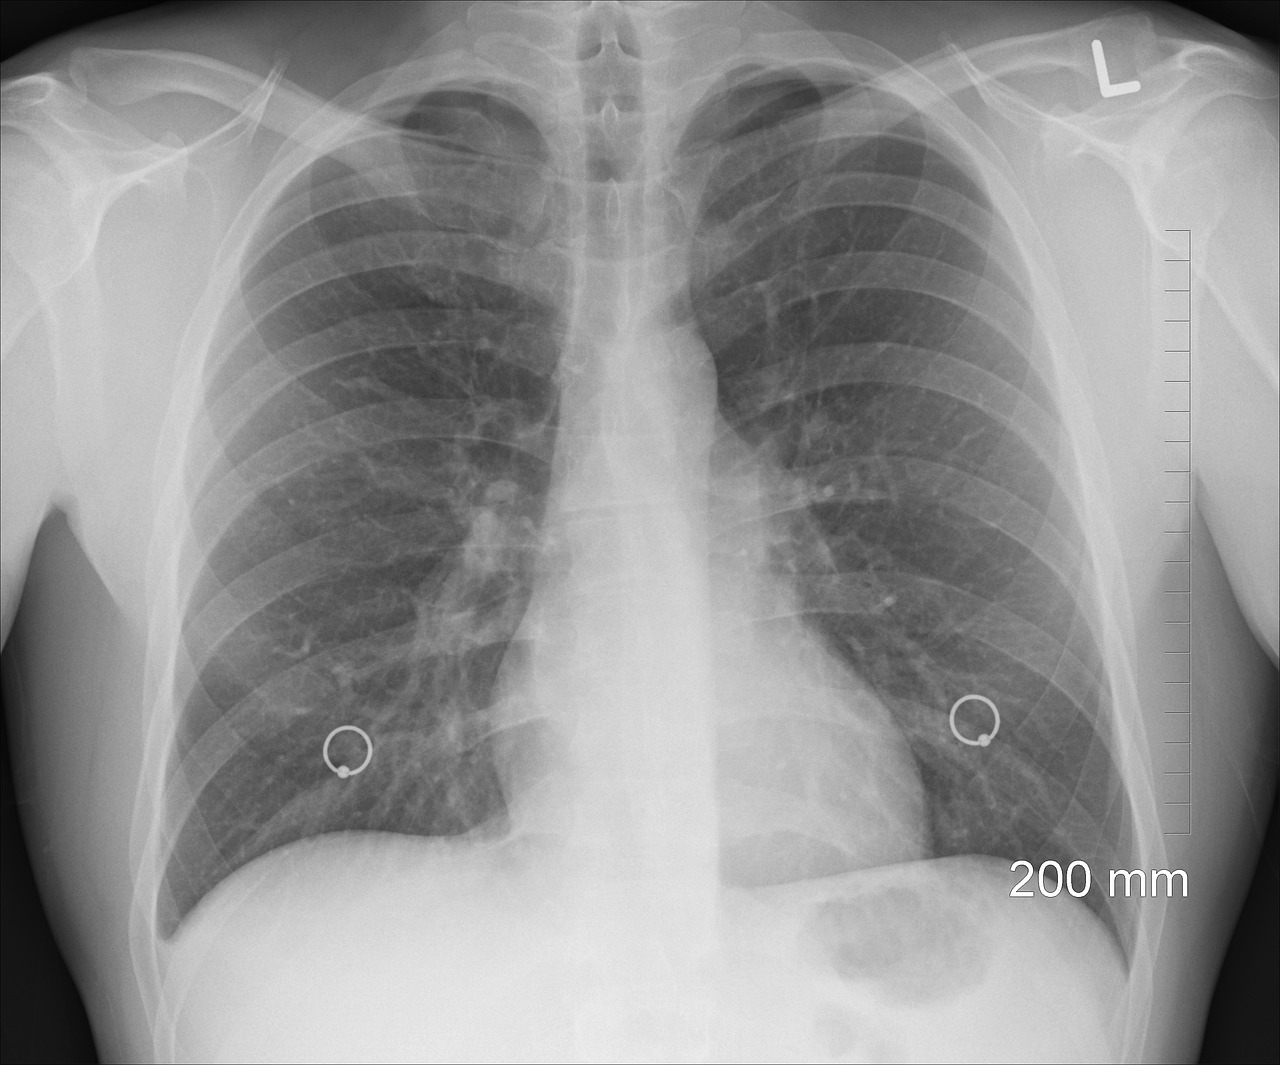

Tuberkulóza v minulom roku zabila 1,23 milióna ľudí

Tuberkulóza zostáva najväčším „infekčným zabijakom“ na svete, keďže vlani pripravila o život 1,23 milióna ľudí. Podľa Svetovej zdravotníckej organizácie (WHO) počet úmrtí klesol v porovnaní s rokom 2023 o tri percentá a počet prípadov o takmer dve percentá. WHO však varuje, že dosiahnuté pokroky sú krehké

pľúca rontgen

Ilustračné foto / Foto: Pixabay

V roku 2024 ochorelo na tuberkulózu odhadom 10,7 milióna ľudí, z toho 5,8 milióna mužov, 3,7 milióna žien a 1,2 milióna detí. Tuberkulózu spôsobuje baktéria, ktorá často infikuje pľúca a je vysoko prenosná, keď ľudia, ktorí ochorenie majú, kašlú alebo kýchajú. Približne štvrtina svetovej populácie má latentnú nákazu tuberkulózou, čo znamená, že v sebe majú baktériu, ale neochoreli a nemôžu ochorenie prenášať.

„Prípady a úmrtia na tuberkulózu klesajú prvýkrát od pandémie COVID-19, ktorá narušila zdravotnícke služby,“ uviedla Tereza Kasajevová, vedúca oddelenia WHO pre HIV, tuberkulózu, hepatitídu a pohlavne prenosné infekcie. Varovala však, že „škrtanie financií a pretrvávajúce faktory epidémie môžu zvrátiť ťažko získané úspechy“ a zdôraznila potrebu politického záväzku, trvalých investícií a globálnej solidarity. Financovanie boja proti tuberkulóze stagnuje od roku 2020. Vlani bolo k dispozícii 5,9 miliardy dolárov, čo je výrazne menej ako cieľ v podobe 22 miliárd dolárov ročne do roku 2027.

Dovedna osem krajín vlani tvorilo až dve tretiny globálnych prípadov tuberkulózy, pričom najviac postihnutá bola India (25 %), nasledovaná Indonéziou, Filipínami, Čínou, Pakistanom, Nigériou, Konžskou demokratickou republikou a Bangladéšom. Päť hlavných rizikových faktorov, ktoré spôsobujú epidémiu, sú podvýživa, infekcia HIV, cukrovka, fajčenie a poruchy spojené s alkoholom.

V minulom roku sa miera úspešnosti liečby zvýšila zo 68 percent na 71 percent. WHO odhaduje, že včasná liečba tuberkulózy zachránila od roku 2000 približne 83 miliónov životov.